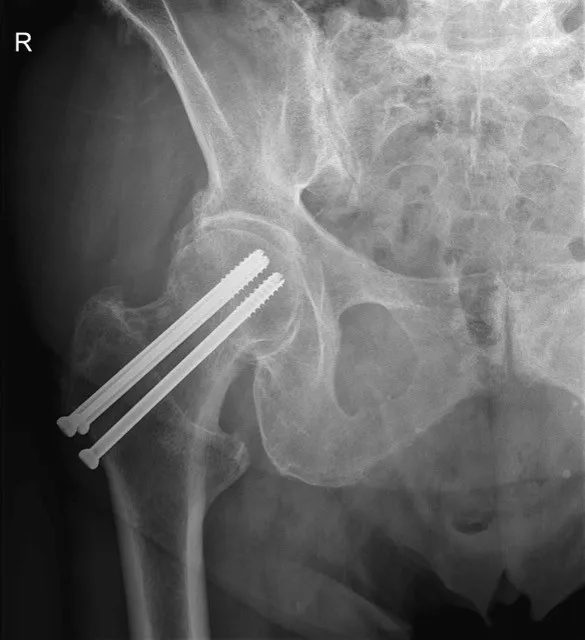

2. Femoral Neck System (FNS) of gecanuleerde schroeven

Bij een subcapitale femurfractuur zonder grote verplaatsing, of bij jongere patiënten, wordt vaak gekozen voor een Femoral Neck System (FNS) of gecanuleerde schroeven. Dit systeem bestaat uit een kort metalen implantaat met schroefconstructie die de dijbeenhals stevig stabiliseert of met drie aparte schroeven. Bij deze ingreep houdt de patiënt zijn eigen heupkop. Het nadeel hierbij is dat de patiënt 6 weken niet mag steunen en dat de breuk in zeldzame gevallen niet geneest.